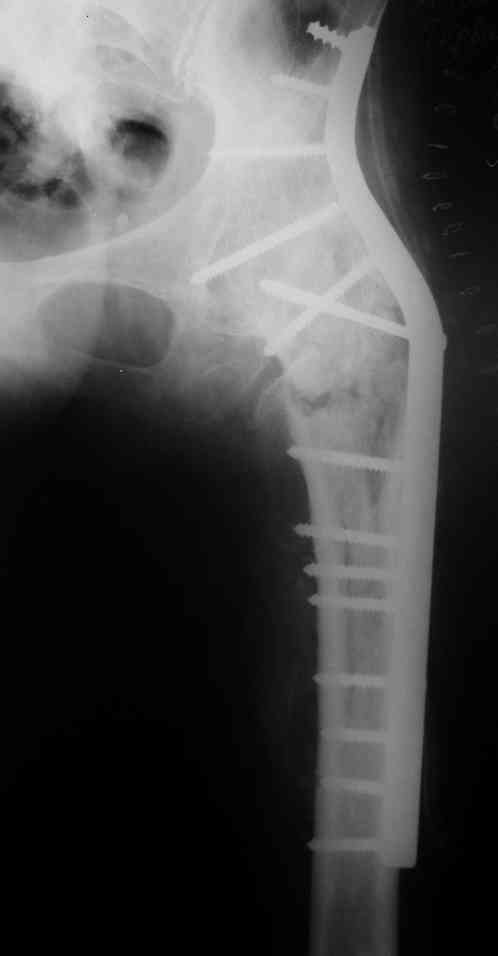

Спасибо за совет и комментарии. Выбор остановили на длинной пластине DCP. Нам показалось, что в нашей ситуации так будет прочнее, по сравнению с клинковой пластиной или DHS.

Рентгенограмму полечили успешно. А какова длина послеоперационного рубца? Проводилась ли гемотрансфузия? На какой день после операции пациент начал ходить? А нагружать оперированную конечность?

Допустим, Вам правильно показалось, и прочность клинковой пластины или DHS, или такого или другого проксимального гвоздя, о чем писал Алексей Семенистый, была бы меньше. Но она была бы достаточной. По крайней мере для ранней нагрузки на ногу. А уж инвазивность уж точно была бы куда меньше, со всеми вытекающими плюсами.

Рентгенограммы до и после. Больной профессор на кафедре сопромата и после детального изучения

особенностей имплантата, собственных рентгенограмм дал добро на операцию. Ваш вариант лечения вполне симпатичен.